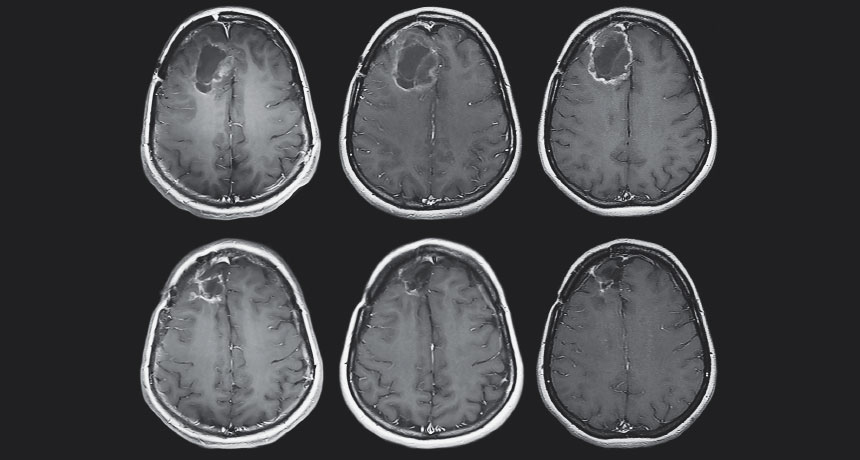

GOING, GOING… These MRI images show a patient’s glioblastoma tumor eventually shrinking after being dosed with an altered poliovirus. The bottom row shows the tumor a year after treatment (left), at two years (middle) and at nearly five years (right).

A. Desjardins et al/New England Journal of Medicine 2018